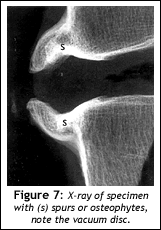

In Figure 6 note the spurs anterior to the disc. My mother notices these structures right off and wants to know what that was even before looking at the desiccated disc. These are bony formations that the body creates in an attempt to stabilize the ever-flattening and desiccating disc. This we can also see on plain x-rays, even though we can't see the disc itself.

The patient is impressed that the disc material extends out as far as the spurs do on the x-ray; she takes to the idea of the disc being the sponge; or that the flat tire or compressed sponge is spreading out around the vertebral body like a pancake; and a light seems to go on! This is not a new concept or idea, but I think some people just don't seem to correlate the two. (For whatever reason, I think I might have gotten through this time.)

I tell mother that the facet joints also lose their joint space by the wearing down of the cartilage forcing the joint capsule, which keeps the synovial fluid and the joint intact to work harder at keeping the unit together. In fact, the joint capsule sometimes works so hard at taking on the extra stress of keeping this joint together that the body starts to form osteophytes, or spurs around the joint capsule in an attempt to hold the joint in its normal position. Of course, when this starts to happen, the joint begins to lose its ability to move normally and again, the whole motor unit starts to break down.